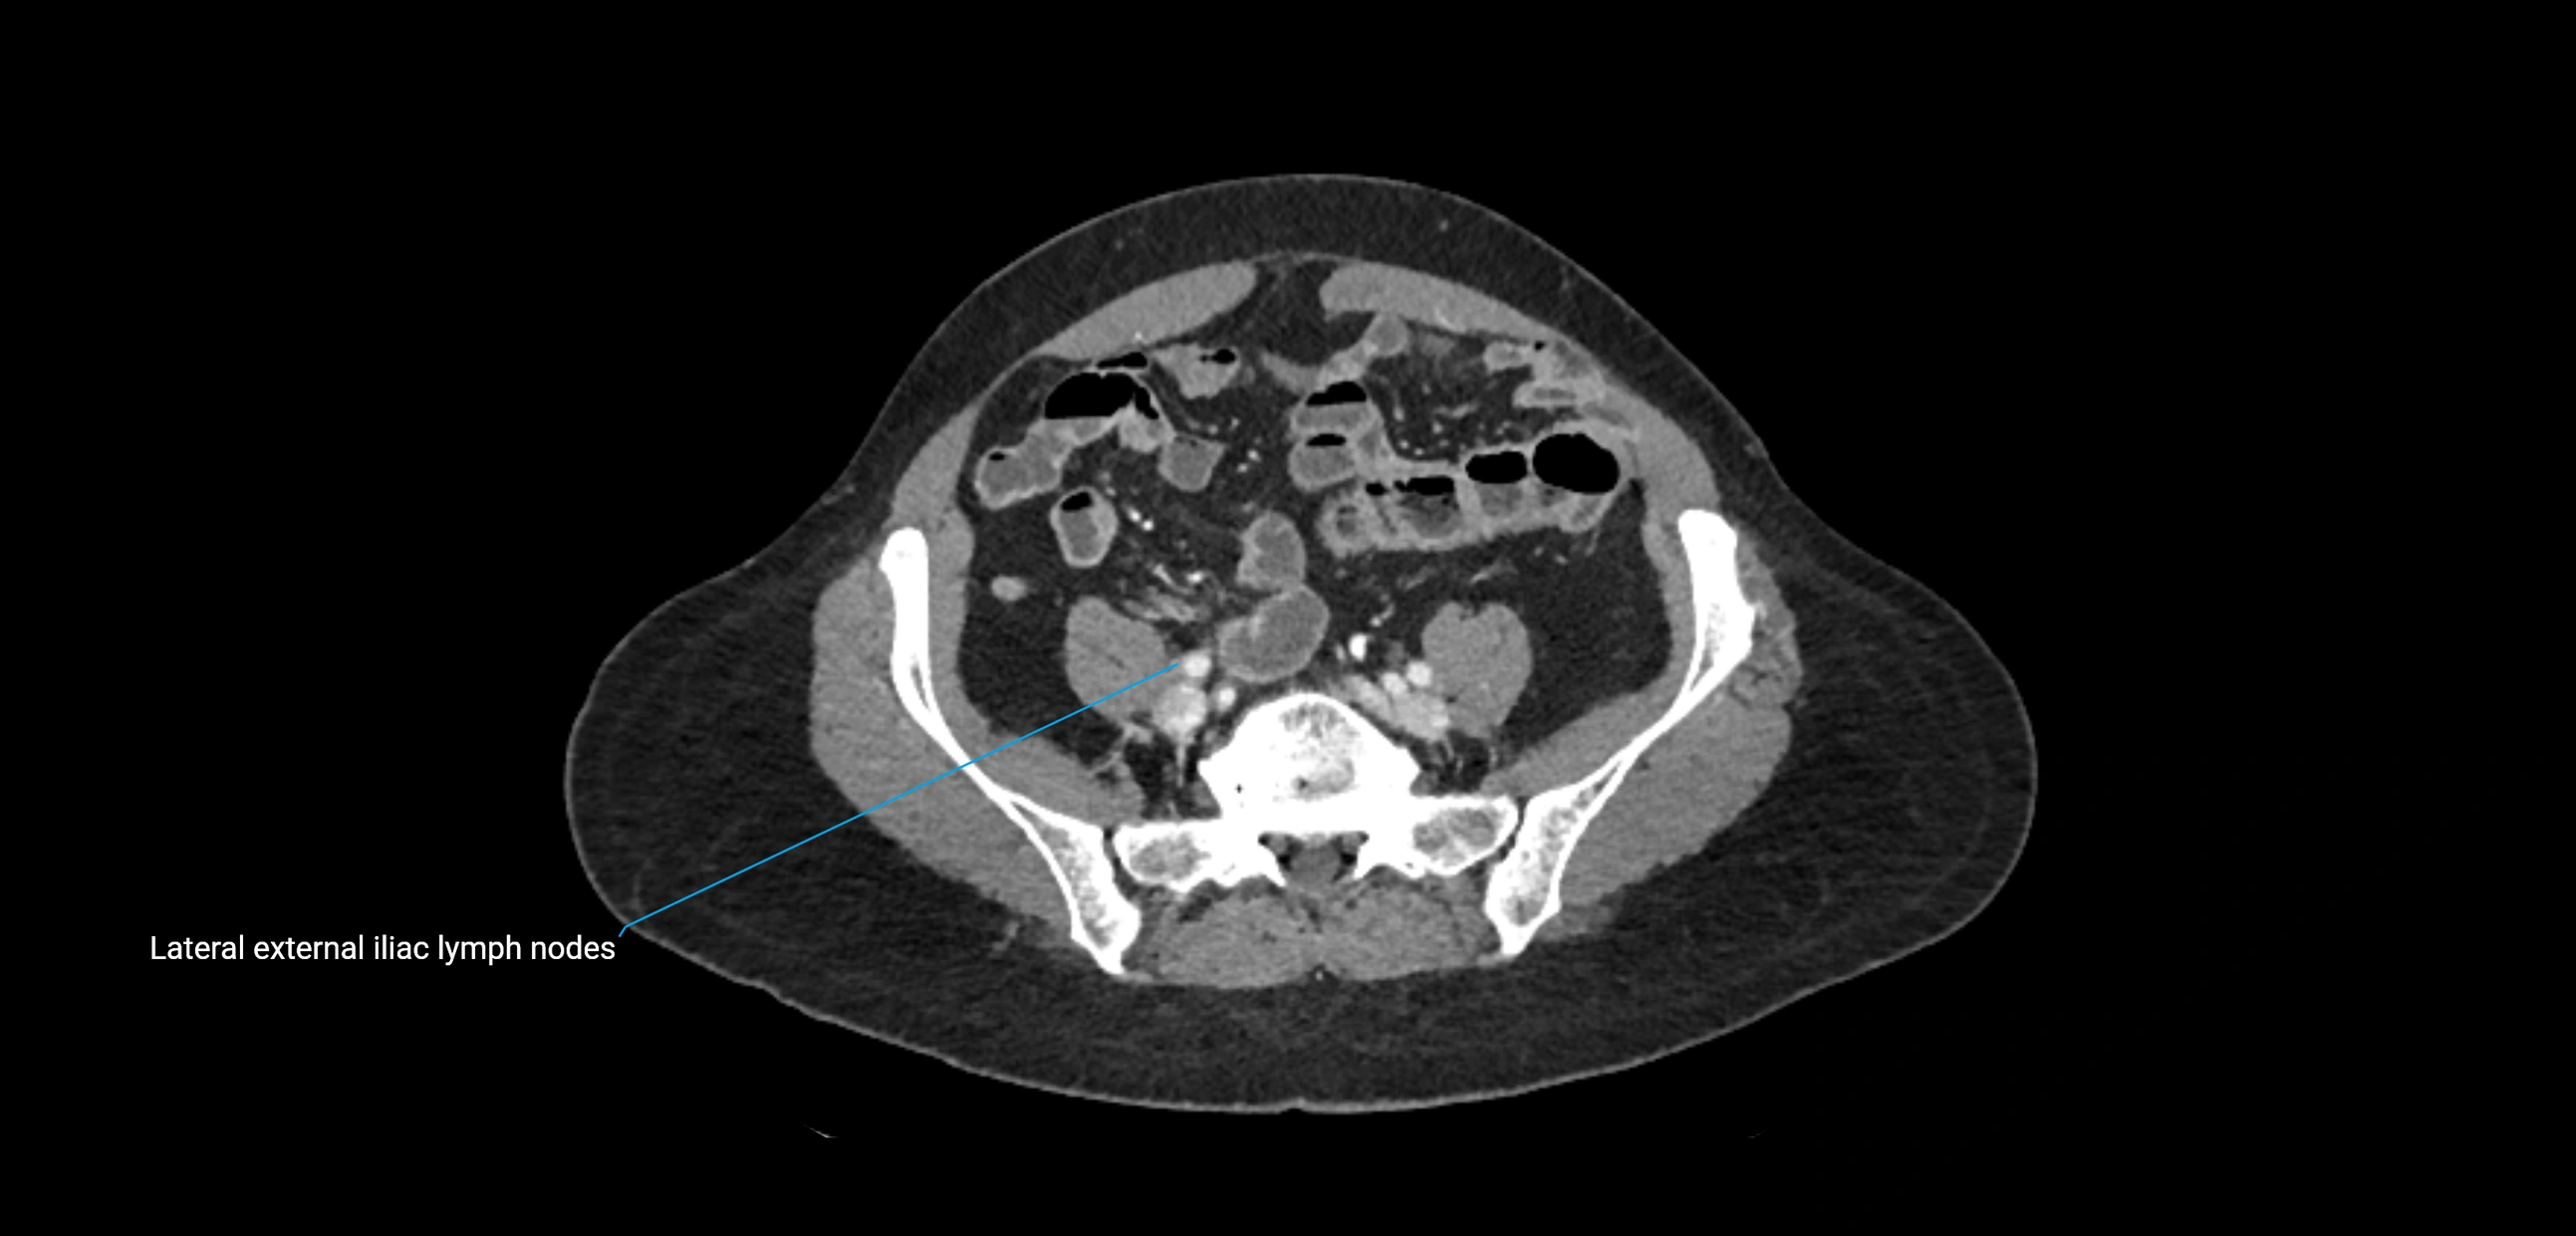

CT Appearance

CT Pre-Contrast:

• Nodes appear as soft-tissue density nodules adjacent to the aorta and IVC

• Calcification may be seen in chronic infections (e.g., tuberculosis)

CT Post-Contrast:

• Normal nodes enhance homogeneously

• Malignant nodes may show heterogeneous enhancement, central necrosis, or conglomerate formation

• Size >1 cm short axis is suspicious, though morphology and distribution are equally important